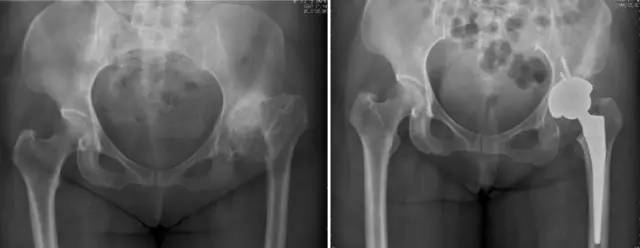

各种晚期骨关节病的关节置换手术治疗是北京清华长庚医院关节外科中心的一大特色,包括股骨头坏死、髋膝骨关节炎、类风湿关节炎、强直性脊柱炎、髋关节发育不良、关节强直、超过80岁的超高龄股骨颈骨折患者的关节置换手术等,我中心在人工关节初次置换及翻修上作了大量工作,置换的难度和手术效果方面已达到国际先进水平,导航下全膝关节置换术:大大提高膝关节置换手术的精确度。

股骨头缺血性坏死

股骨颈骨折